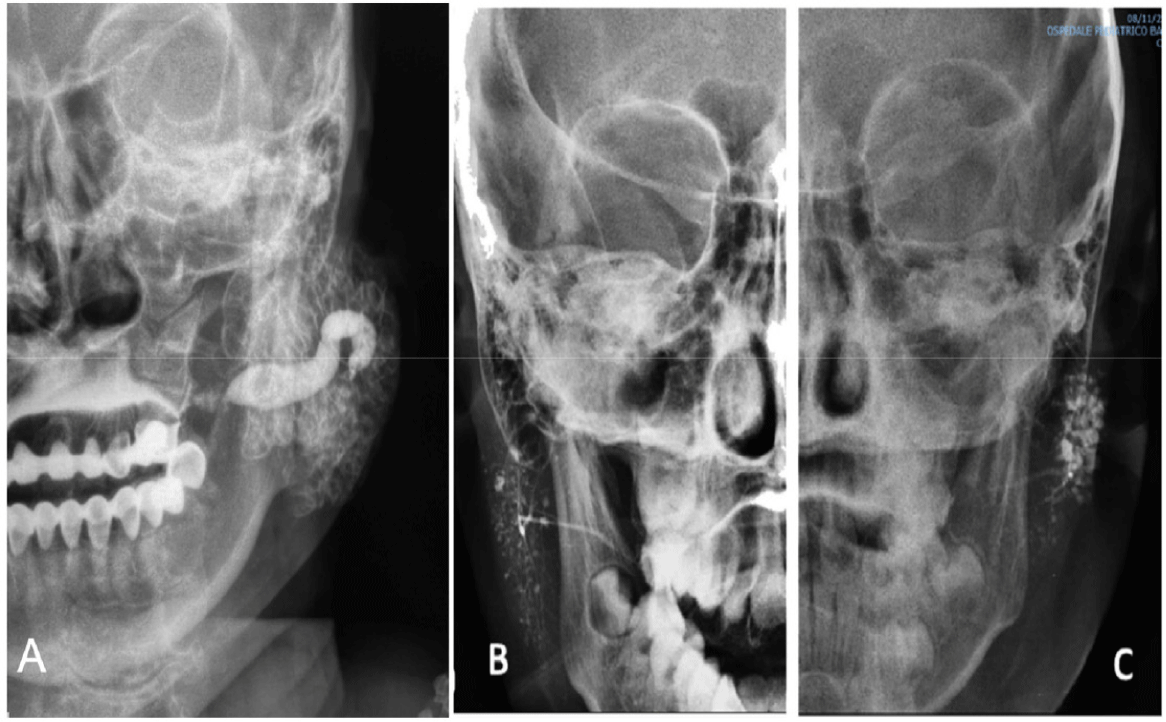

Imaging: Sialography is an effective diagnostic method that provides detailed imaging of ductal dilation or obstruction within the salivary gland system. This technique can identify characteristic dilation patterns, such as punctate sialectasis, globular sialectasis, or a sausage-like appearance [36]. Additionally, modern imaging modalities such as CT and MRI are also used to detect chronic lesions and rule out other causes, such as glandular tumours or autoimmune diseases. The combination of these imaging techniques allows for a comprehensive and accurate assessment of salivary gland abnormalities (Fig. 4) [39] .